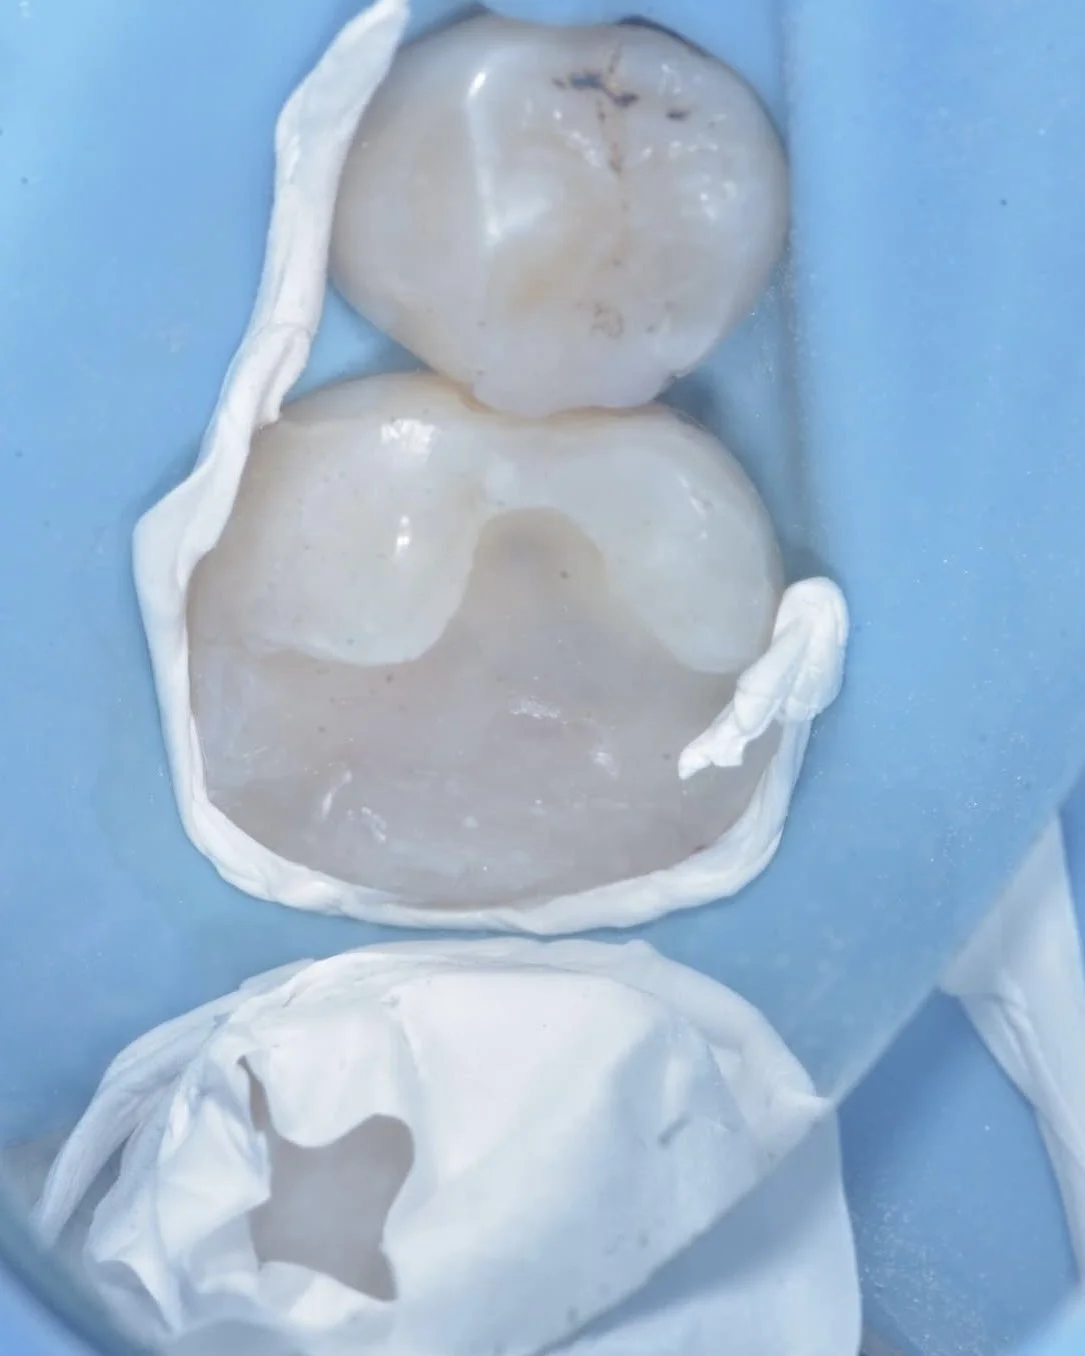

Here are two examples of caries removal endpoints (CRE) in this case by Dr. Davey Alleman, DMD. Complete caries removal was possible on the left tooth, while the right tooth required partial caries removal to preserve the pulp vitality.

This case by Dr. Davey Alleman, DMD shows the process of removing caries around the pulp to create a caries-free peripheral seal zone.